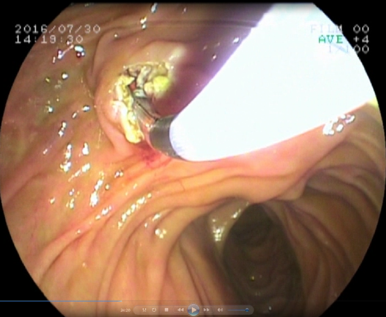

2. 内镜精准到达胆管开口

4. 根据病变选择取石/放支架等治疗